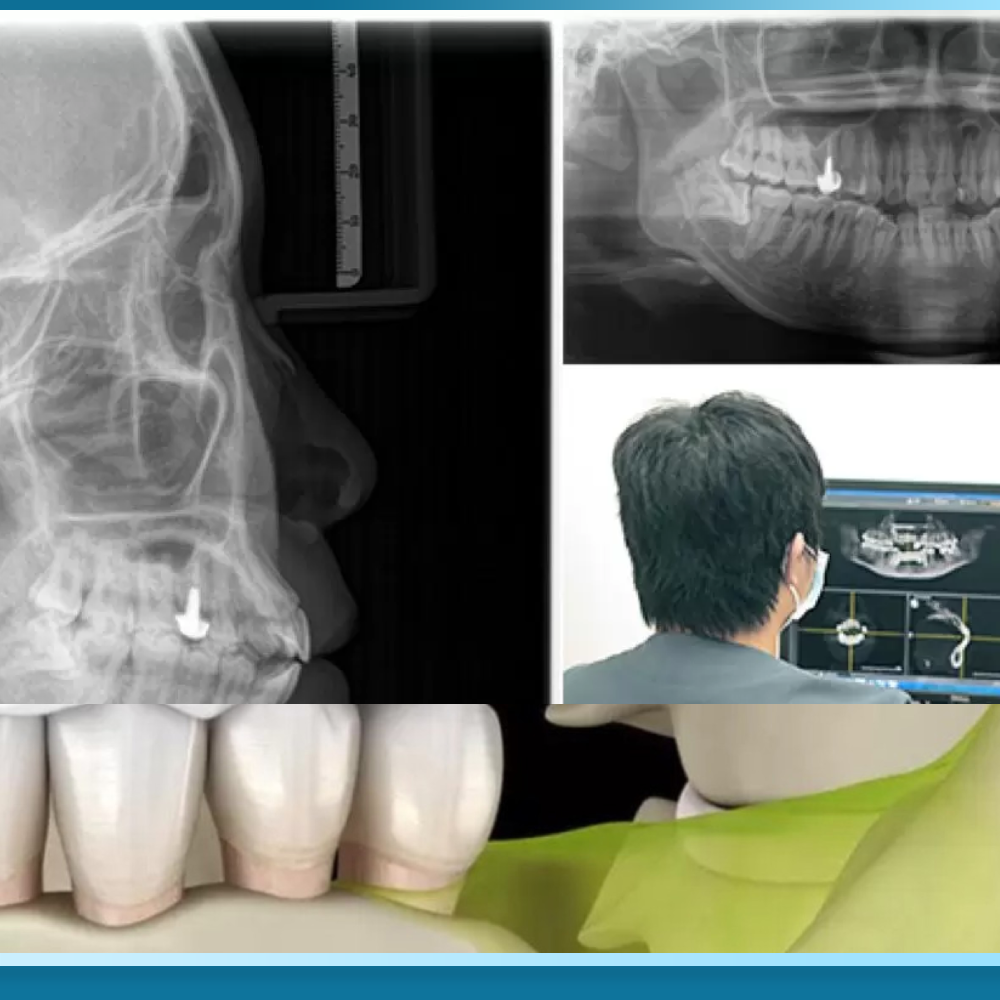

Đánh giá mật độ xương qua phim CT Cone Beam trước khi cấy ghép

Phim chụp CT Cone Beam 3D là công cụ chẩn đoán hình ảnh không thể thiếu để xác định khả năng thực hiện Trồng răng Implant All on 6. Công nghệ này cho phép bác sĩ quan sát cấu trúc xương hàm theo không gian ba chiều, đo lường chính xác chiều cao, chiều rộng và đặc biệt là mật độ xương thông qua chỉ số Hounsfield (HU). Dựa trên phân loại của Misch, mật độ xương được chia thành bốn loại từ D1 đến D4.

Trong quá trình khảo sát phim CT, bác sĩ cũng sẽ đánh giá vị trí của xoang hàm và các ống thần kinh. Đối với những bệnh nhân mất răng lâu năm, xoang hàm thường có xu hướng sa xuống thấp, làm giảm đáng kể chiều cao xương ở vùng răng hàm trên.

Nếu kết quả phim chụp cho thấy chiều cao xương còn lại dưới 5-6mm, việc đặt thêm hai trụ phía sau cho All on 6 sẽ trở nên bất khả thi nếu không có các thủ thuật bổ trợ. Việc đánh giá kỹ lưỡng qua phim CT Cone Beam giúp loại bỏ các yếu tố suy đoán cảm tính, đảm bảo rằng mỗi ca phẫu thuật đều được lập kế hoạch dựa trên các dữ liệu khoa học chính xác nhất, từ đó tối ưu hóa tỷ lệ thành công của quá trình tích hợp xương.